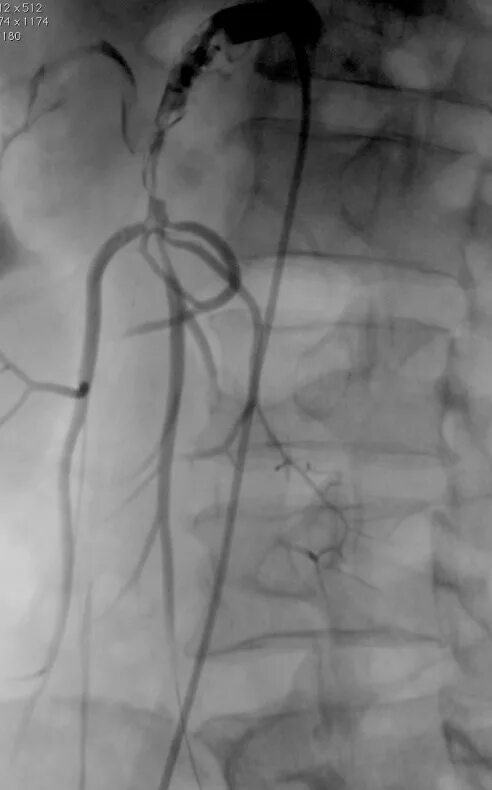

Тромбоз брыжеечной артерии